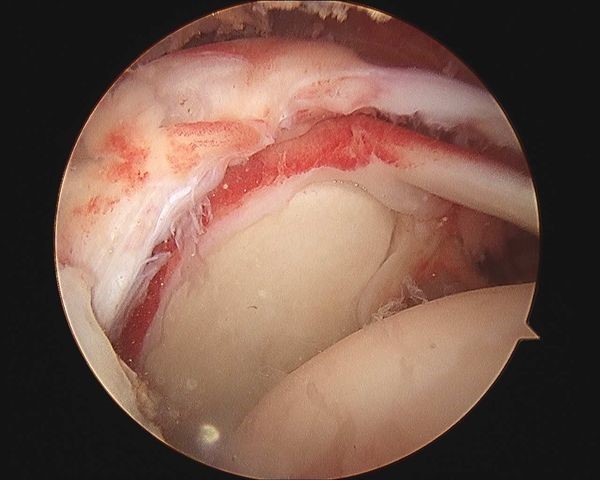

肩关节镜下炎性、增生组织清理